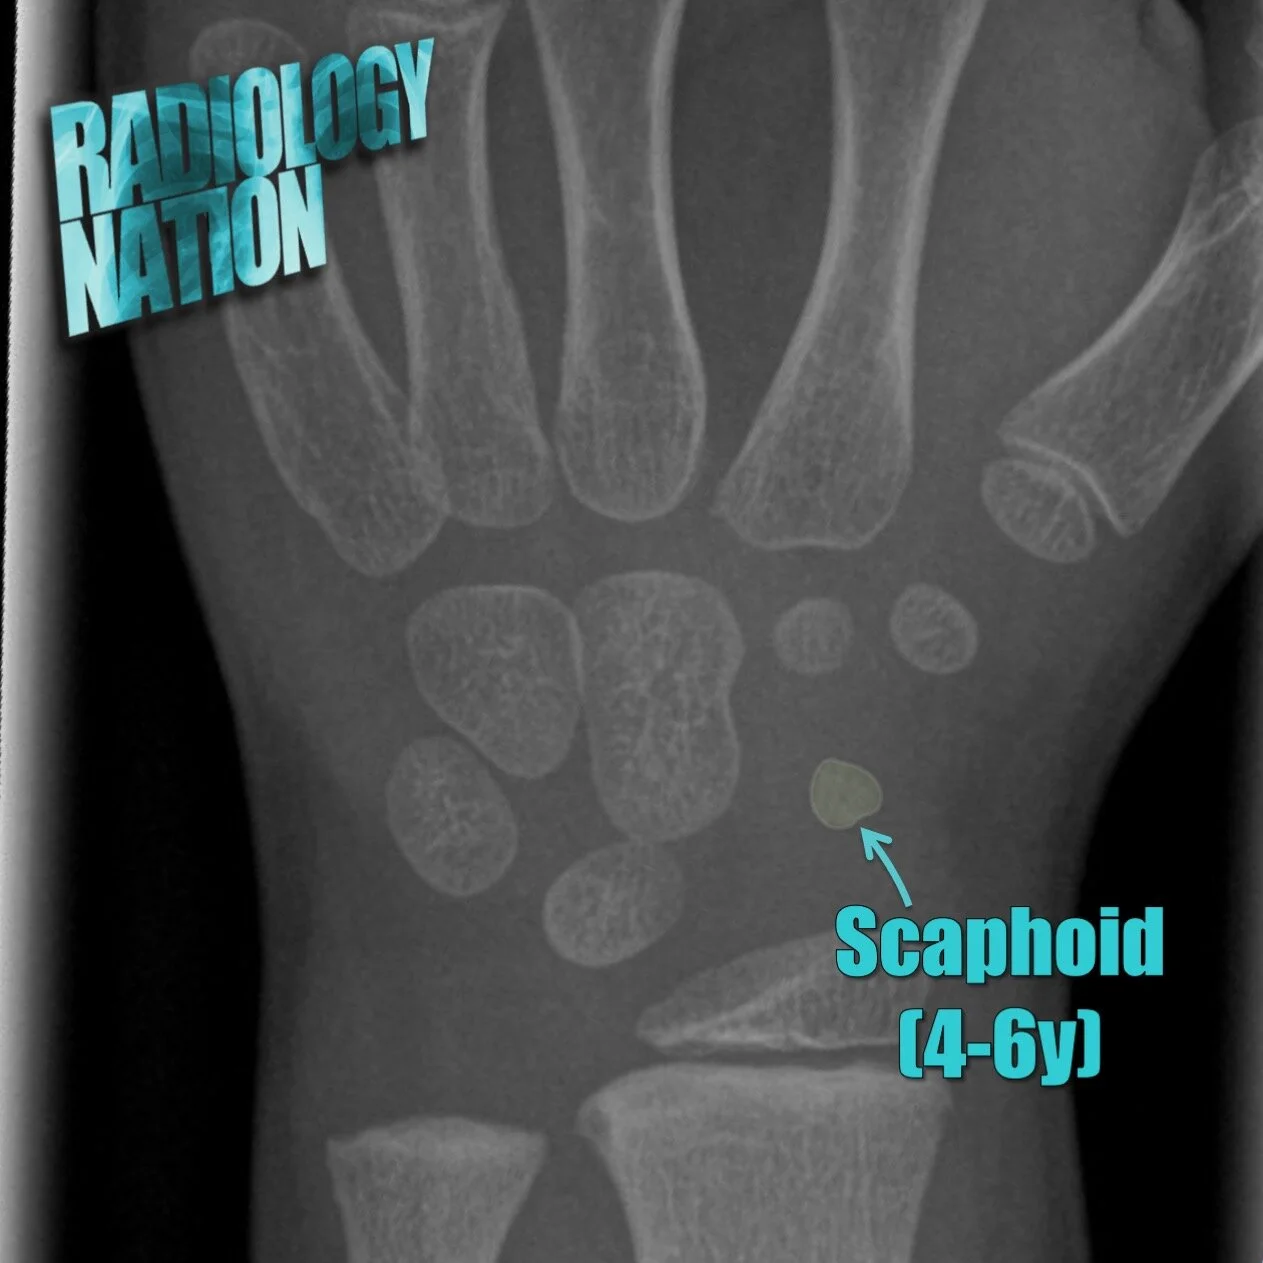

Musculoskeletal Radiographs

Visual guides to radiographic image interpretation

Musculoskeletal Radiology Tutorials

On this page we have a series of image based tutorials for you to teach yourself musculoskeletal radiology!